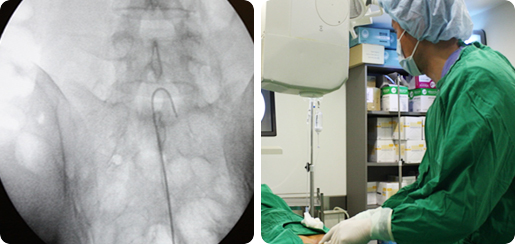

경막외 유착박리술

추간판탈출증 또는 요추관협착증이 있을 때 신경주위 염증 또는 유착이 발생하여 허리통증이나 하지 방사통이 발생하여 신경치료로도 호전이 잘 안 되거나 수술적 치료를 하였으나 유착이 발생하여 증상이 재발할 때 실시간 방사선촬영하에 특수 카테터를 척추관 내에 넣어 염증과 유착이 일어난 신경 주변을 박리하고 약물을 주입하여 염증을 완화하고 유착을 풀어주는 치료입니다. 카테너 삽입부위의 국소마취를 이용하여 치료 후 바로 보행이 가능하며 허리디스크, 척추협착증에 효과적이며 재발성 디스크, 수술 후 유착에도 시술할 수 있습니다.